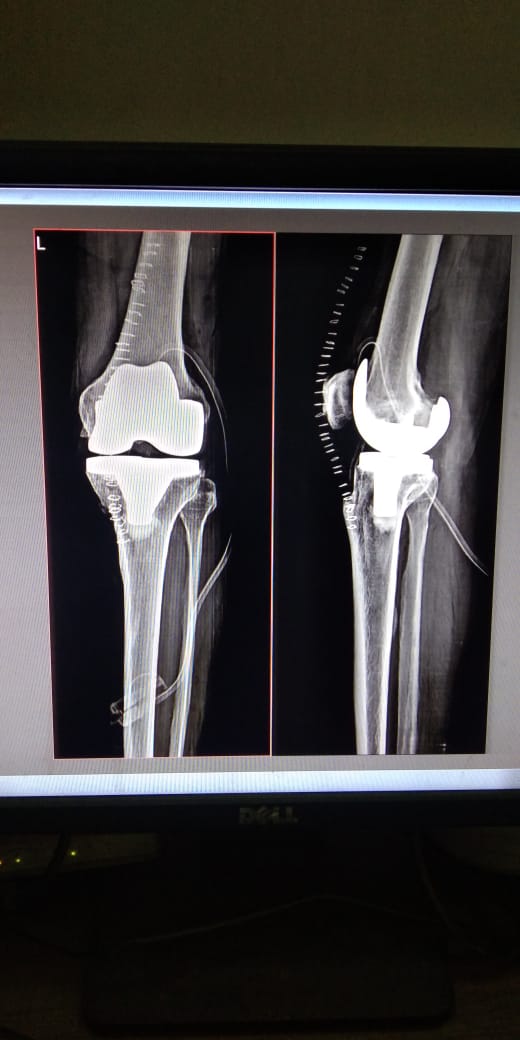

Catherine Chettiar [ Revision Total Knee Replacement ]